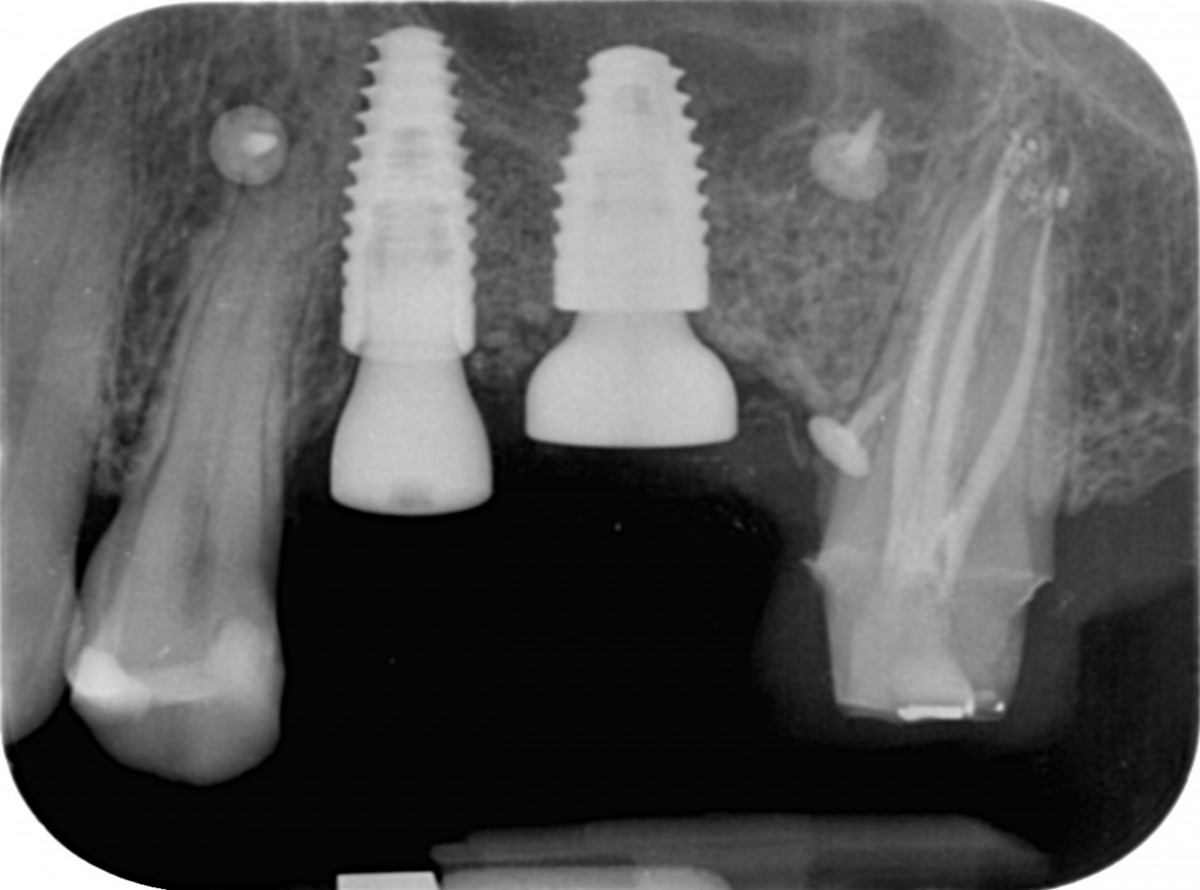

The tomographic cuts obtained (Fig. 6 and Fig. 7) allowed the accurate evaluation of the residual bone volumes and the adjacent anatomical structures not otherwise appreciable in the two-dimensional view of the site, allowing the operator to insert the implants in complete safety and full compliance of the patient's anatomy (Fig. 8)